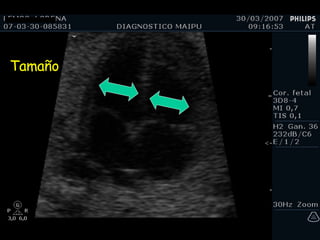

Tamaño

EN SINTESIS Constatar que tiene corazón Que está en el tórax Que late Evaluar situs Magnificar la imagen Reconocer las cámaras Evaluar los tabiques Evaluar ritmo 3 vasos